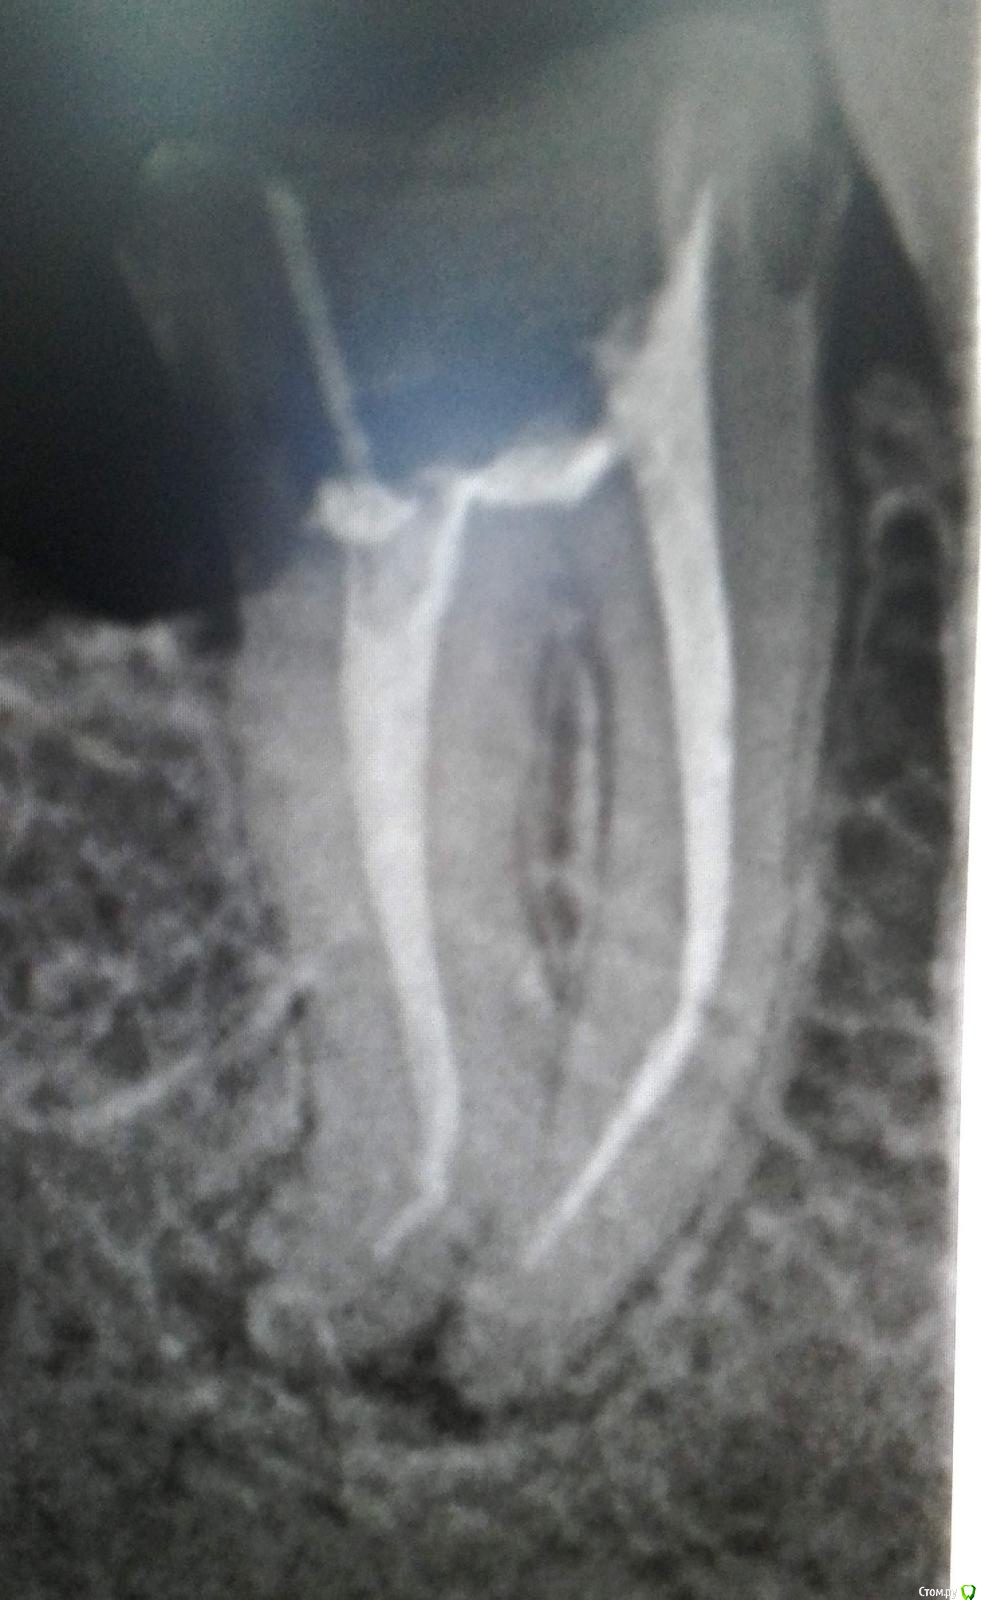

dentifree Опубликовано 14 февраля, 2015 Поделиться Опубликовано 14 февраля, 2015 Здравствуйте,есть проблема с зубом. 7-ка, нижняя справа.реагирует на постукивания, легкой болью,жевать не больно.иногда ощущается давление в зубе., особенно на физич. нагрузки тренировки.лимфоузел в районе этого зуба, твердый, дотронуться больно,.. но терпимо. снимок сделан в 2015 году, обратился в стоматологии, мнения разделились 50\50 - лечить\удалять. http://s020.radikal.ru/i707/1502/dc/c7116bed6d52.jpg зуб этот делался ранее в 2011 году,.. вот снимок во время лечения,.. если это может как-то внести больше ясности. с состоянием корней. http://s015.radikal.ru/i331/1502/2f/0c5515d1f5ad.jpg Ссылка на комментарий

dentifree Опубликовано 10 февраля, 2016 Автор Поделиться Опубликовано 10 февраля, 2016 спасибо за ответ. )год так тянул.в этом месяце попытка перелечить. пройти корни до конца. на снимке, вроде как не совсем пройдены. далее пройти нет возможности ?док говорит, там какой-то прибор сообщает, о том что корень пройден, ну или выход за предел корня, через стенку. ? после чистки корней, на следующий день была боль, решили пить антибиотики. помогло. за 3 дня.в итоге сейчас, на надавливание не болит, а на легкие постукивания реагирует, легкой болью.получается что очаг воспаления не побежден ?смущает, что удалось ли пройти корни, а то там фрагмент сосуда остался, он источник восполения ? после удалениия пульпы,.. какая дальнейшая жизнь сосудов корня ? Ссылка на комментарий

St. Опубликовано 10 февраля, 2016 Поделиться Опубликовано 10 февраля, 2016 По снимку все неплохо. в итоге сейчас, на надавливание не болит, а на легкие постукивания реагирует, легкой болью. получается что очаг воспаления не побежден ? После лечения возможен легкий дискомфорт. Со временем должно пройти. Наблюдайте за зубом и через 6 и 12 мес сделайте контрольные снимки.Только обсудите со своим врачем как будет восстановлен зуб и когда, чтоб не получилось что на год с временной пломбой пропали. Тогда все усилия по спасению зуба пропадут.. после удалениия пульпы,.. какая дальнейшая жизнь сосудов корня ? Пульпа - это упрощенно и есть сосуды и нервы.Для Вас как для пациента это ненужные технические нюансы. Ссылка на комментарий

shishok Опубликовано 10 февраля, 2016 Поделиться Опубликовано 10 февраля, 2016 на снимке, вроде как не совсем пройдены. далее пройти нет возможности ? Канал может открываться не точно на верхушке,а сбоку(что чаще всего и бывает).Поэтому на Rg-снимке кажется,что каналы пройдены не до конца. Ссылка на комментарий